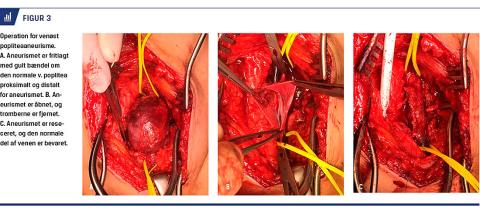

Operationen foregår via en længdegående adgang bag på benet. I de fleste tilfælde er der udført tangentiel aneurismektomi og lateral venorafi under en længdegående kartang (Figur 2) [13, 25]. På denne måde bevares et lumen af venen, der svarer til den normale vene proksimalt og distalt for aneurismet. Kun hvis der er tromber i aneurismet, er det nødvendigt først at åbne det og fjerne tromberne (Figur 3). Denne operation er specielt velegnet til sakkulære aneurismer, men den

er også udført ved fusiforme aneurismer [3, 5]. Alternativet er at foretage interposition af et stykke vene sv.t. aneurismet eller at foretage resektion af hele aneurismet med ende til ende-anastomose af venen [2, 3,

5, 20]. Postoperativt er der anvendt en kompressionsstrømpe i en periode [3, 5, 20] og AK-behandling

i 3-6 måneder [2]. Af postoperative komplikationer

får enkelte mindre hæmatomer eller sårinfektioner.

N. ischiadicus med delingen i n. tibialis og n. peroneus communis ligger ofte spændt ud over aneurismet og må mobiliseres, hvilket forklarer, at enkelte får forbigående dropfod [2]. Kun få af karrekonstruktionerne lukker i det postoperative forløb, og der er en tendens til, at det går bedst efter tangentiel aneurismektomi [2]. Selv om enkelte patienter har været fulgt i mere end ti år, er observationstiden dog ofte kun få år [2]. Der er aldrig beskrevet nye tilfælde af lungeemboli efter en operation [2, 5]. Men seks patienter har fået recidiv af aneurismet efter 1-8 år [2, 8, 22], heraf blev fire reopereret med en ny karrekonstruktion.